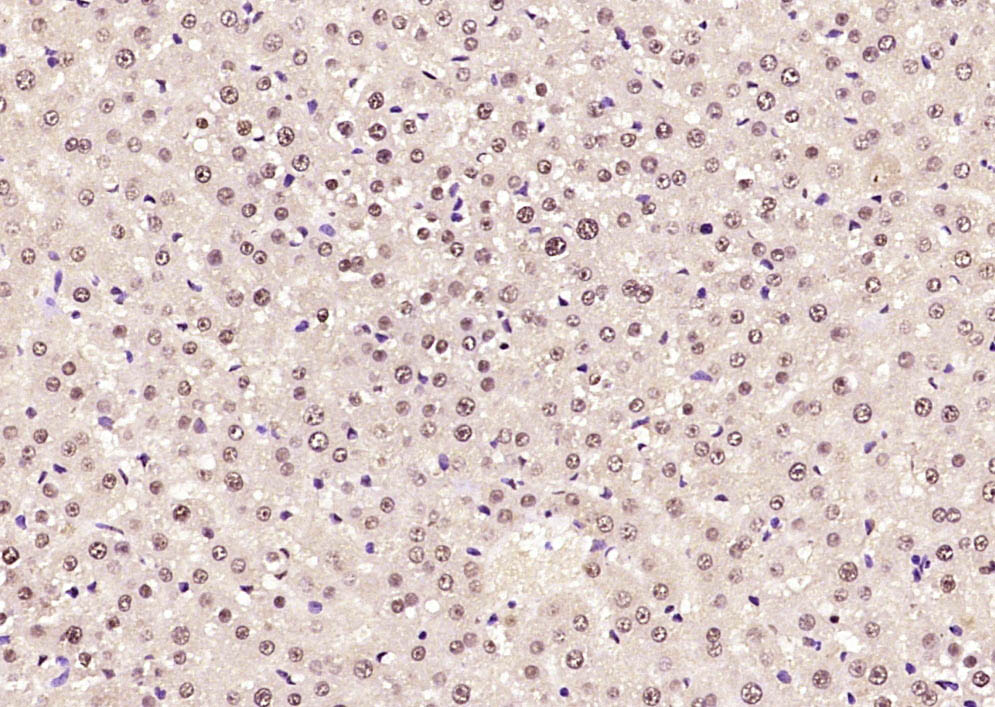

Paraformaldehyde-fixed, paraffin embedded Human colon cancer; Antigen retrieval by boiling in sodium citrate buffer (pH6.0) for 15min; Block endogenous peroxidase by 3% hydrogen peroxide for 20 minutes; Blocking buffer (normal goat serum) at 37°C for 30min; Antibody incubation with SOX9 Polyclonal Antibody, Unconjugated (bs-10725R) at 1:400 overnight at 4°C, DAB staining.